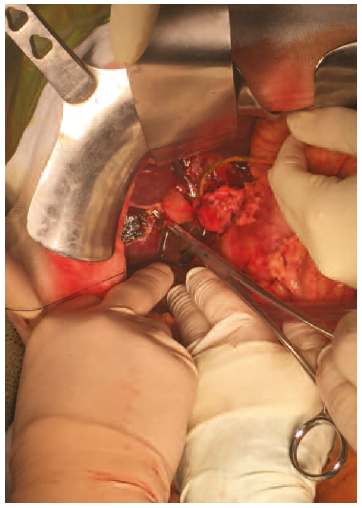

The patient required surgical revision. Intraoperatively scarce bile was observed in the Morrison space, with intact biliary anastomosis and correctly placed T tube. Cholangiography was performed, as usual, injecting contrast through the Kehr catheter. This allowed contrast leak to be observed through the graft’s cystic duct stump on cholangiography. After that, surgical revision was carried out. Serum saline was injected trans-Kehr during the surgical intervention to verify the cholangiography findings and to identify the origin of the leak. Primary suture of the defect was performed (Figure 1). An intraoperative cholangiography showed no other points of leakage and showed contrast passage into the native common bile duct and duodenum, using augmented pressure due to bile duct diameter discrepancy (Figure 2). Previous failure of endoscopic management and the reduced diameter of the native bile duct resulted in need for biliary bypass surgery with Roux-en-Y hepaticojejunostomy.

Figure 1. Primary Suture of Cystic Duct Stump in Graft